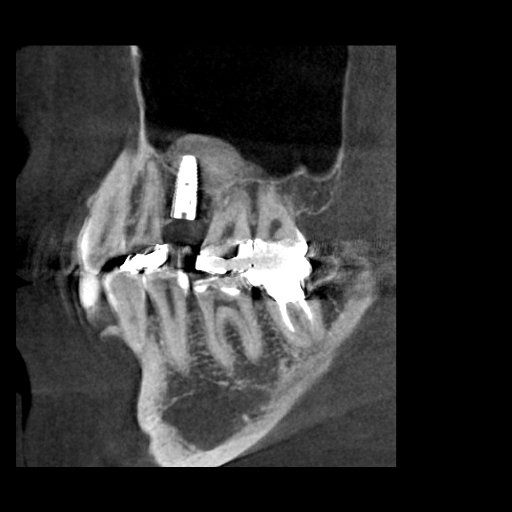

右下奥歯のインプラント症例

Before

• 右下6番欠損です。

• インプラントを埋入するのと同時にヒーリングキャップを取り付けました。

After

治療内容

右下の奥歯を根の先の膿が原因で抜歯された患者様です。

ブリッジ治療では両隣の歯を大きく削らないといけない為、インプラント治療を希望されました。

骨の治り方が歪で、頬側の骨が大きく足りないため骨造成を行い、インプラントを埋入した日にヒーリングキャップを装着し、インプラントが骨と結合するまで待ちます。

その後、型取りをし被せ物をスクリューにて装着しています。

担当歯科医師:平沼 佳朗

治療期間・回数

約10か月

費用

骨造成込み ¥616,000

リスク・副作用

術後に痛みや腫れ、出血を伴います。

口腔内の清掃不良によりインプラントの歯周病(インプラント周囲炎)になる可能性があります。定期的なメインテナンスが必要です。